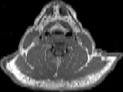

Visible Human male: Sectio transversalis 1241

CT

NMR

Pd T1 T2